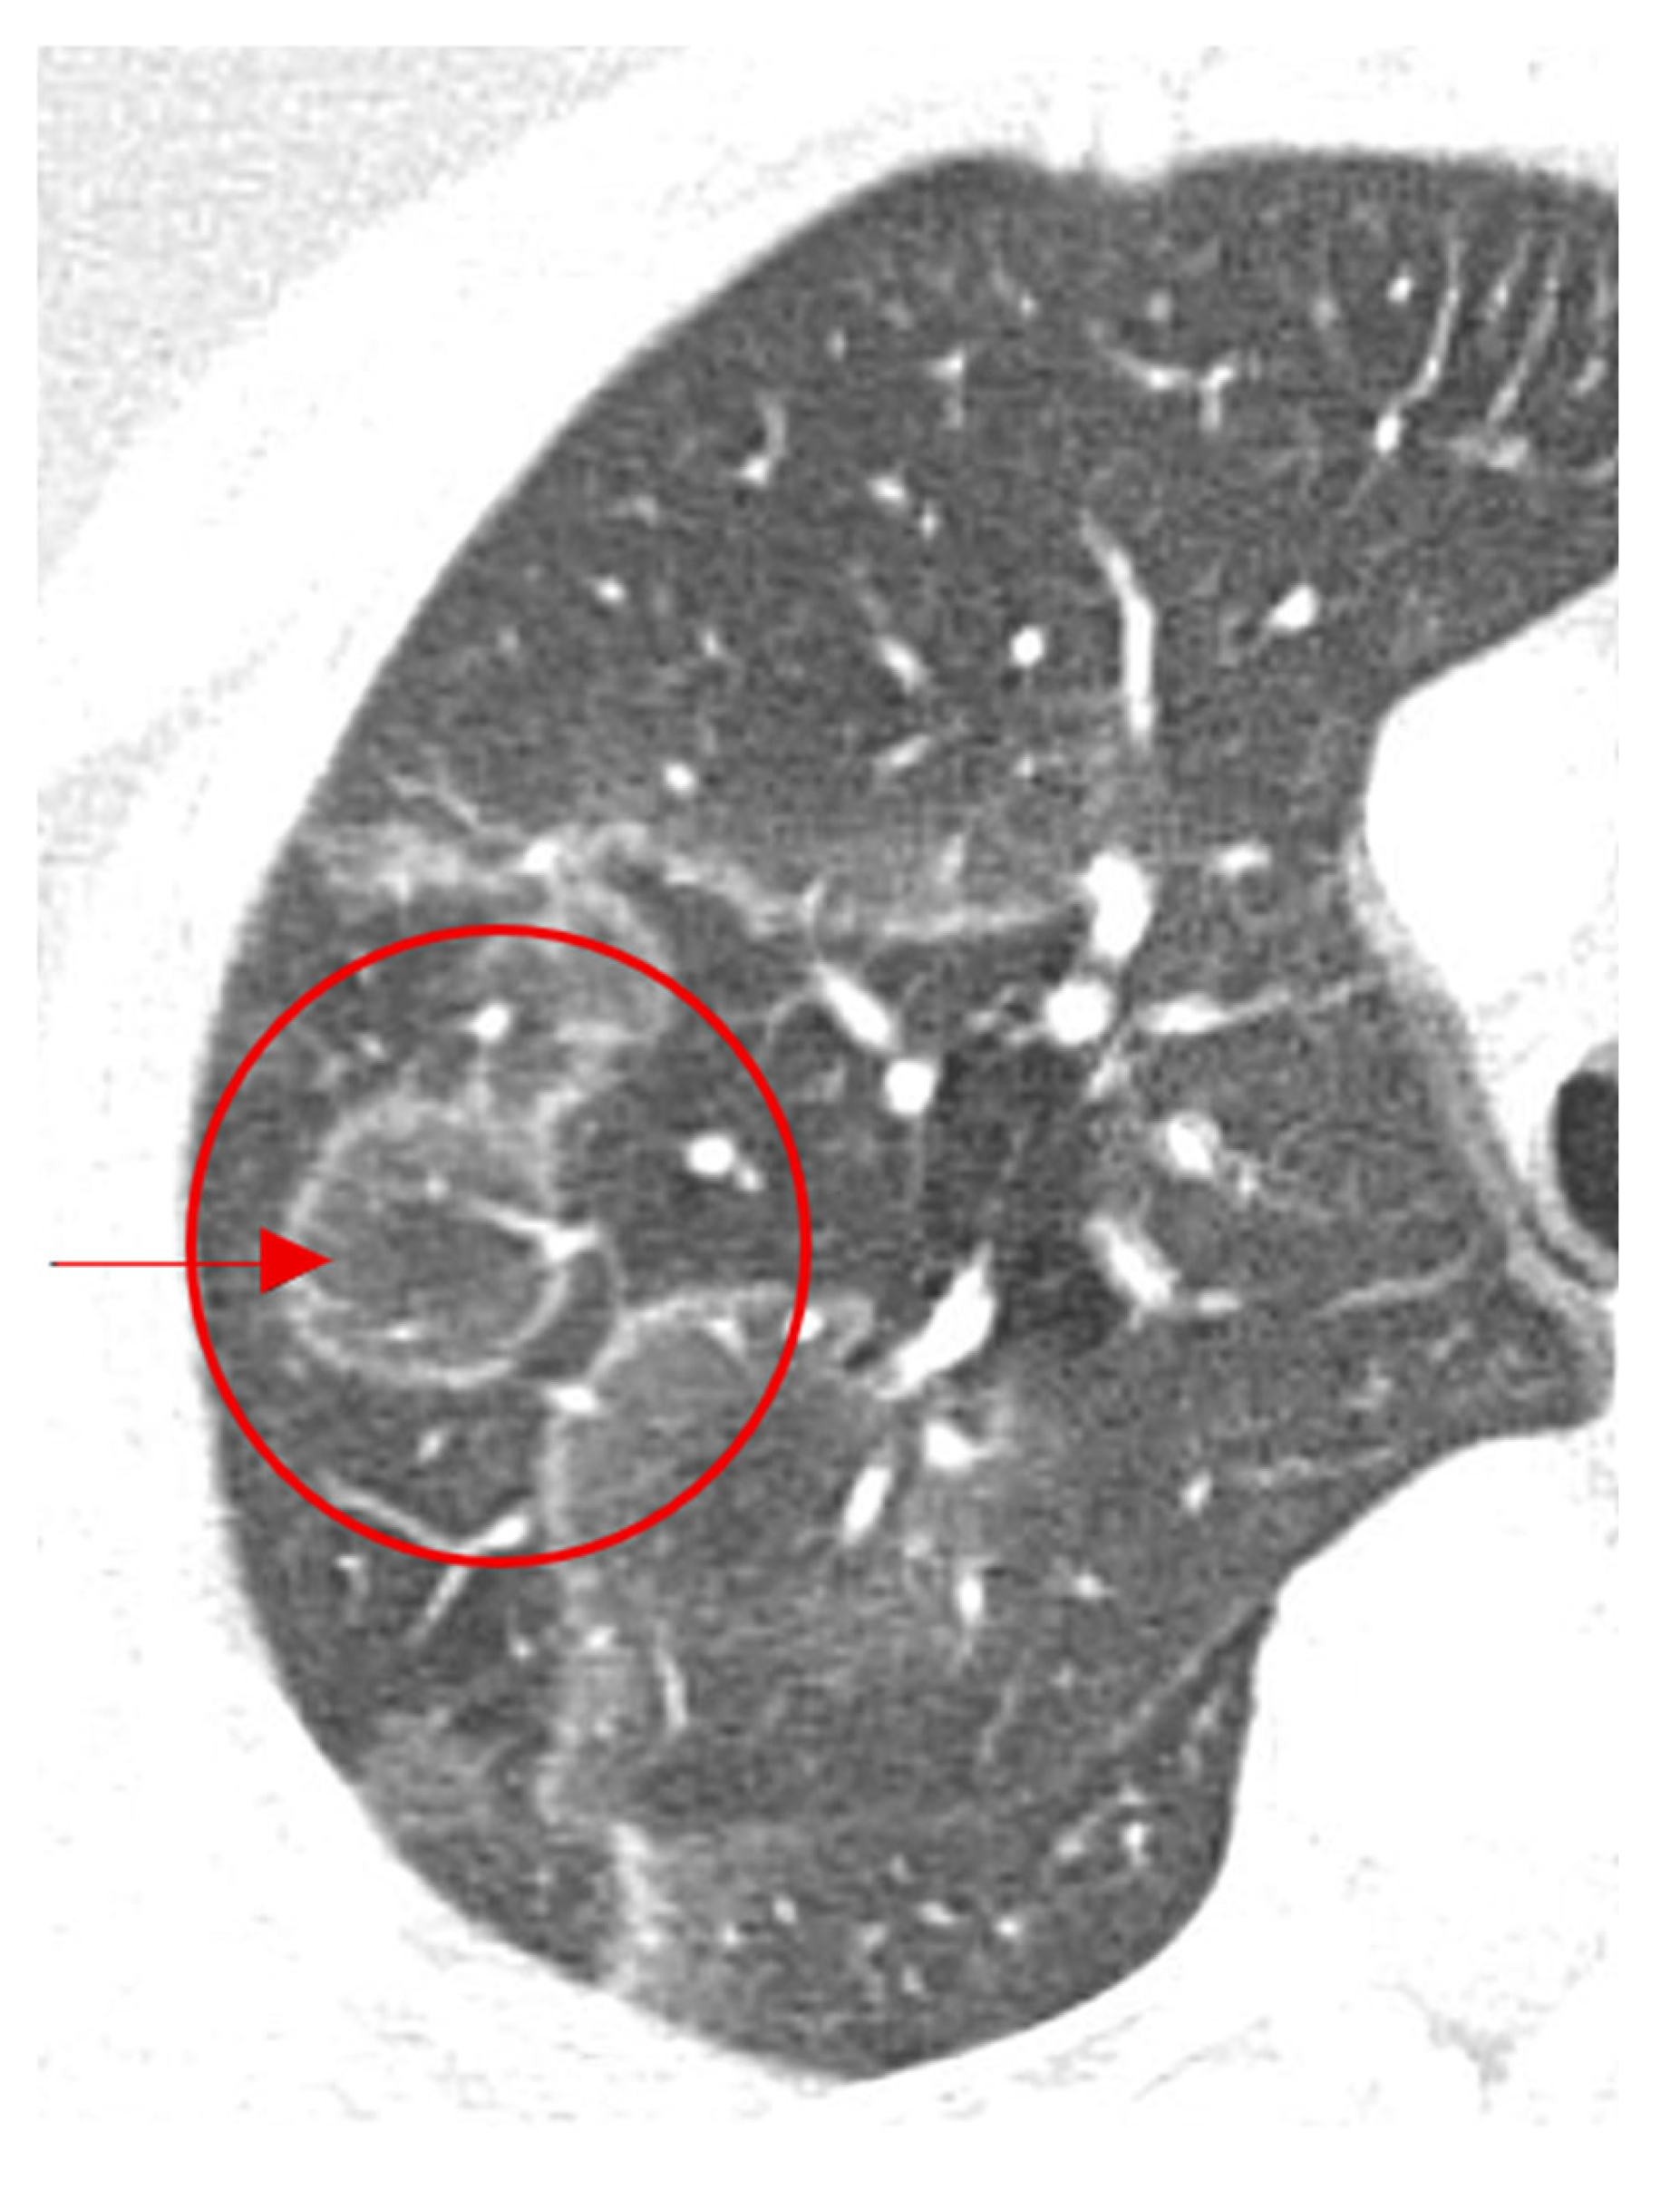

2.3. Galaxy Sign

This sign is seen on chest CT in multiple granulomatous diseases and malignancies, and it is most known to be a feature of pulmonary sarcoidosis [20]. Mimicking the appearance of a galaxy (Figure 3a), it appears as a large pulmonary parenchymal nodule, typically located along the lymphatics, formed by the coalescence of smaller non-caseating granulomas (proven by radiologic-pathologic correlation [21]), with tiny satellite low attenuations nodules more apparent at the periphery, (Figure 3b) [20]. In a Japanese single-center cohort, the galaxy sign on CT had a sensitivity of 23.1% and a specificity of 98.1% for distinguishing pulmonary sarcoidosis from tuberculosis, highlighting its low sensitivity but high diagnostic specificity in appropriate clinical settings [22]. In rare instances, it may be associated with cavitation and ground glass attenuations [21]. In patients with respiratory or systemic symptoms suggestive of sarcoidosis, a galaxy-like nodule composed of confluent granulomas supports the diagnosis and guides further staging and extrapulmonary evaluation.

Figure 3.

An image depicting a far galaxy (a) with resemblance to the CT view of the chest showing mass-like regions composed of numerous smaller granulomas with a central core and peripheral nodules seen in sarcoidosis (red arrows) (b).